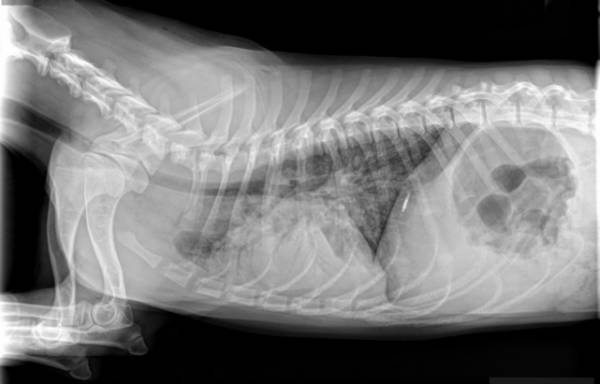

Виключно в умовах гарної ветеринарної клініки! Там ветеринар збере повний і достовірний анамнез, зробить рентгенограму грудної порожнини. Все це дозволить повністю виключити наявність інших захворювань у тварини. Крім того, у разі хронічного бронхіту, напевно доведеться брати зразок патологічного матеріалу та проводити бактеріологічний посів. Тільки так можна підібрати дієве лікування.